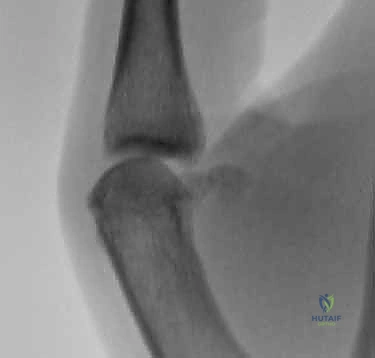

3. التصوير الإشعاعي (Imaging)

لا يكتفي الأستاذ الدكتور هطيف بالفحص السريري، بل يعتمد على التصوير لتأكيد التشخيص واستبعاد الإصابات المصاحبة:

* الأشعة السينية (X-rays): تُجرى دائماً قبل اختبار الإجهاد لاستبعاد وجود كسور (مثل الكسر القلعي - Avulsion fracture، حيث ينفصل جزء صغير من العظم مع الرباط الممزق).